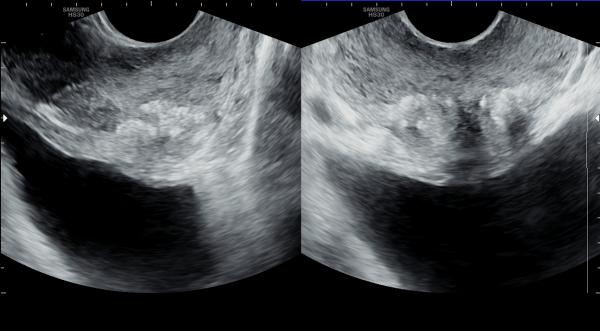

수년전부터 하복부 통증과 배뇨장애와 빈뇨와 급밥뇨가 심해 개인 비뇨기과와 상급의료기관에서 치료를 했으나 증상의 호전이 없고 최근 두달전 증상이 심해져 내원 당일 경직장 초음파 검사상 좌우 사정관 입구의 결석이 심하고 오래전부터 막혀 전립선의 이행구역과 주변 구역까지 결석이 침습된 전립선 사진입니다.

For several years, the patient had been experiencing lower abdominal pain, urinary dysfunction, frequent urination, and urgency. Despite receiving treatment at private urology clinics and tertiary medical centers, there was no improvement in symptoms. On the day of the visit, a transrectal ultrasound examination revealed severe calcification at the openings of both ejaculatory ducts. The ducts had been chronically obstructed, allowing the calcifications to invade the transition zone and surrounding areas of the prostate.

내원 당일 측면 경직장 전립선 초음파 사진과 정면 경직장 전립선 초음파 사진입니다.

These are the sagittal and frontal transrectal ultrasound images of the prostate taken on the day of the initial visit.